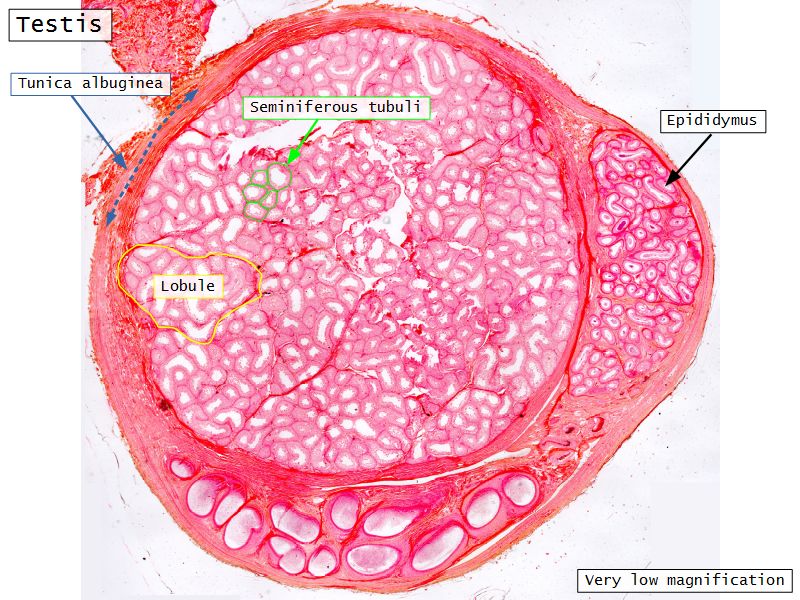

Testis

Slide 84

Testis

- Tunica albuginea

- Lobuli

- Seminiferous tubuli

- Epididymus

- Ductus deferens

Tunica albuginea

- Thick fibrous CT capsule

- Forms septae

- Divide testis into lobuli

Lobuli

- Pyramidal shaped compartments

- Contain 1 - 4 seminiferous tubules each within

Seminiferous tubuli

- Site of spermatozoa production

- 150 - 250 µm diameter

Epididymus

- Long convoluted duct

- With fibrous covering

- Inside visceral layer of tunica vaginalis testis